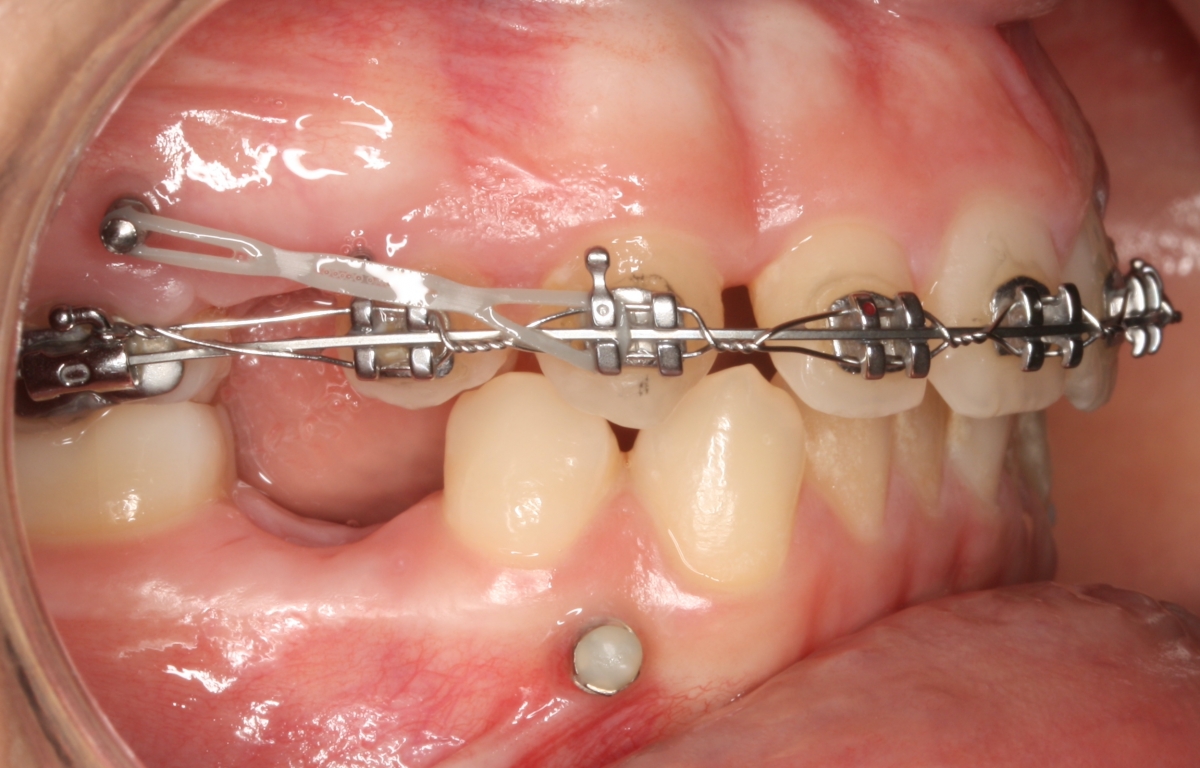

Os microimplantes  interradiculares são pequenos parafusos que se colocam  com anestesia local no osso,  entre as raízes dos dentes. São usados para facilitar determinado tipo de movimentos, realizando-se estes de uma forma mais rápida e controlada. No final do tratamento de ortodontia são removidos, não existindo qualquer tipo de complicação.